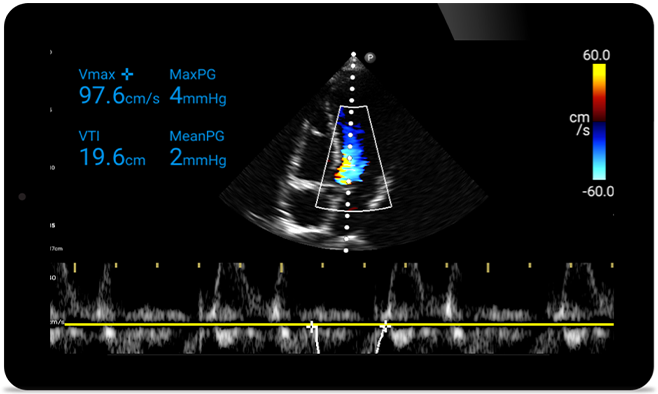

Schneller reagieren, das Herz schützen

Wenn jede Sekunde zählt, kann mobil einsetzbarer Ultraschall den entscheidenden Unterschied machen. Lumify bietet die hochauflösenden Bilder, die Sie benötigen, an jedem Ort und zu jeder Zeit.

Fallstudie

An Opportunity to potentially reverse cardiomyopathy (Möglichkeit zur potenziellen Umkehr von Kardiomyopathie)

Intro to transthoracic echocardiography (Einführung in die transthorakale Echokardiographie)